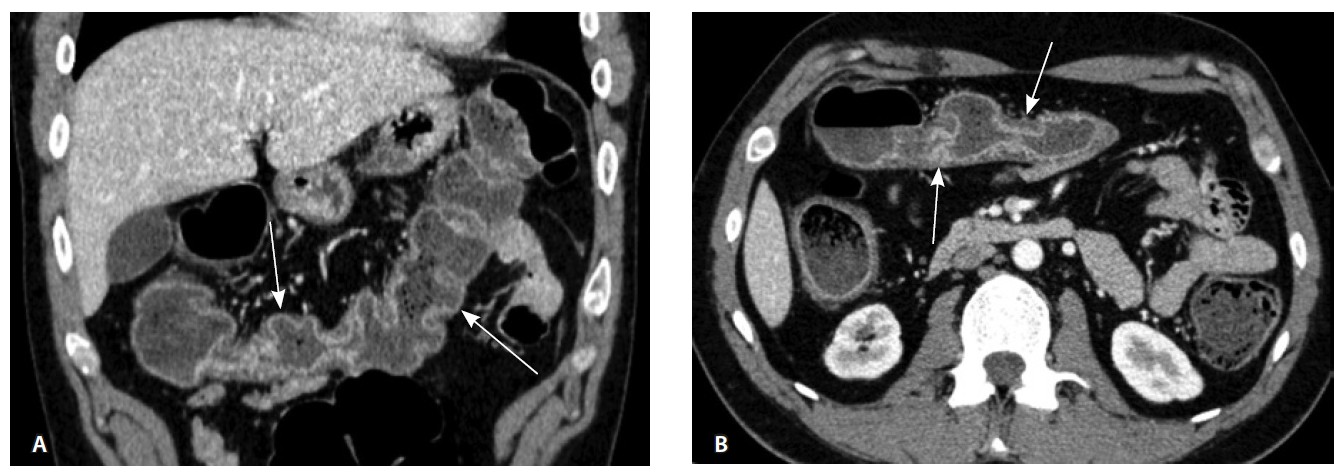

Одним из условий проведения процедуры ВИСТ-АТГСК было отсутствие септических очагов, в связи с чем выполнено углубленное исследование перианальных поражений БК. По данным магнитнорезонансной томографии органов малого таза выявлен простой аноректальный свищ. За месяц до начала режима кондиционирования проведена санация параректального свища (установка дренажа-сетона), тогда же выполнено последнее п/к введение препарата устекинумаб. По данным контрольной илеоколоноскопии подтверждена активность болезни (рис. 4).

Рис. 4. Контрольная илеоколоноскопия. Слизистая оболочка толстой кишки с изменениями: А – щелевидные и полигональные эрозии (стрелка), Б – поверхностная язва диаметром до 0,5 см (стрелка)